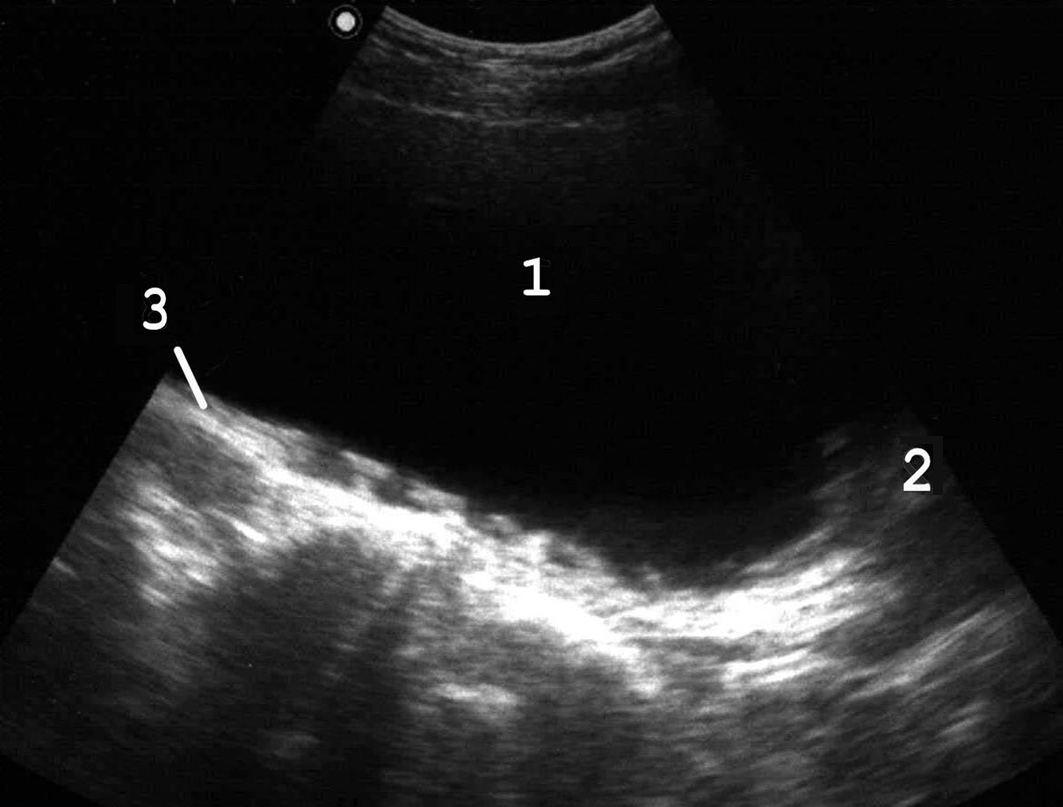

Рис. 6. В дальнейшем появляется трабекулярность его стенок: 1 − мочевой пузырь; 2 − простата; 3 − стенка пузыря утолщена, с выраженной трабекулярностью. (Продольное сканирование, конвексный датчик 5 МГц, “Logiq-500”).